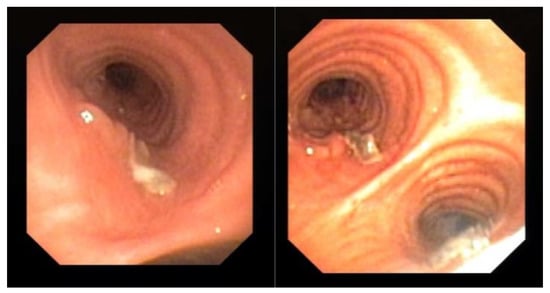

Endoscopic examination through bronchoscopy may also reveal the presence of lesions (i.e., epithelial plaques, pseudomembranes, or ulceration of the bronchial mucosa) that may not be detectable by radiologic exams. We observed these findings in one patient with COVID-19 (Figure 1). These lesions resembled lung cancer infiltration and only bronchial biopsy allowed a correct diagnosis of CAPA.

Evidence of mucosal infiltration and pseudomembranes in the left main bronchus, in a COVID-19 associated pulmonary aspergillosis (CAPA). The patient underwent a bronchial biopsy for the histological diagnosis.